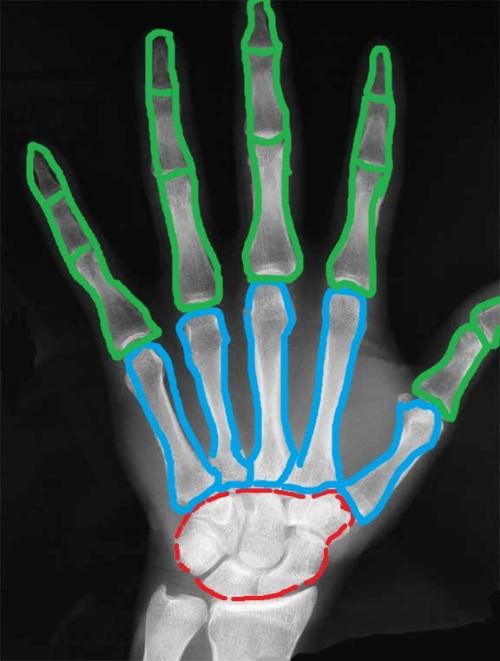

Я решил немного раскрасить этот скучный рентгеновский снимок. Красным цветом я выделил запястье, голубым — пясть, а зелёным — кости пальцев (фаланги).

Кости запястья (ossa carpi)

К костям запястья относят восемь маленьких плотных косточек, которые располагаются в два ряда — проксимальный и дистальный . Чтобы не запутаться в них, следует придерживаться принципам, которые я описывал в статье о том, как учить анатомию человека .

На этом рисунке я я выделил красным цветом проксимальный ряд костей запястья, а зелёным — дистальный.

А теперь давайте сориентируемся на настоящем рентгеновском снимке и попробуем на нём найти проксимальный и дистальный ряды костей запястья (цвета такие же):